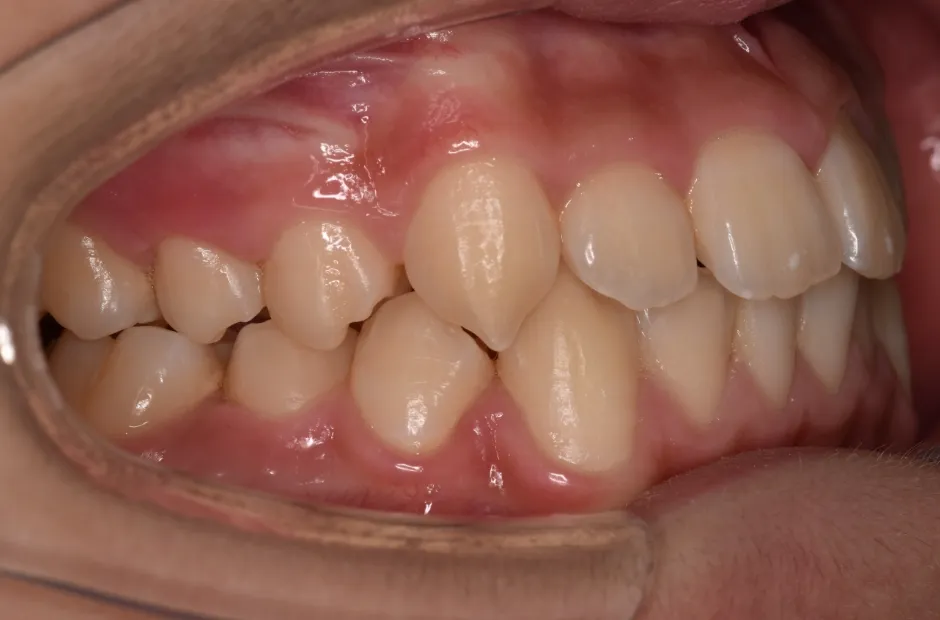

拡大床装置

叢生

| 診断名・主訴 | 叢生 |

|---|---|

| 年齢・性別 | 10歳・女性 |

| 治療期間・回数 | 2年半 |

| 治療に用いた主な装置 | 拡大床装置 |

| 抜歯部位 | なし |

| 治療費 | 30万円(税抜) |

| リスク・副作用 | 装置による違和感・疼痛・歯肉退縮・歯根吸収・虫歯のリスクなど |

治療前

治療中

治療後